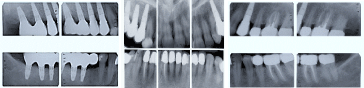

Her existing dental restorations included ceramic crowns with inadequate occlusal contacts and defective margins on all maxillary posterior teeth as well as mandibular left first and second molars. The crowns on her mandibular incisors were esthetically compromised due to their opaque appearance, as compared to their adjacent teeth. She was missing her mandibular right first and second molars which were replaced by an acrylic resin provisional fixed partial denture for the time being (Figure 1).

Figure 1. Preoperative panoramic radiograph.